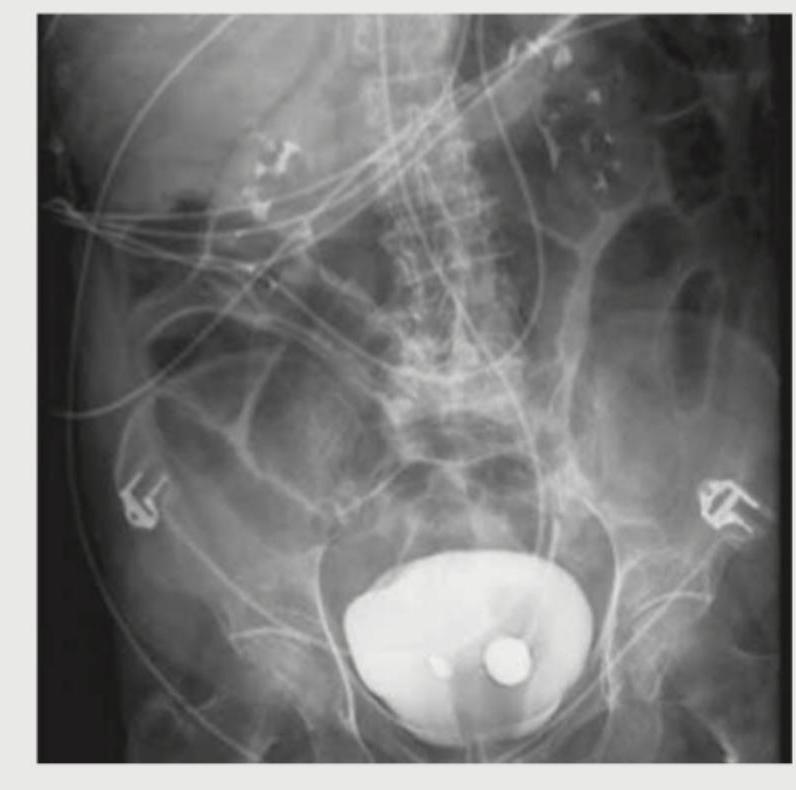

A 26-year-old construction worker with a previous history of recurrent kidney stones presents with flank pain. What is the radiological sign demonstrated in the IVP image shown below?

Question 15: A 26-year-old construction worker with a previous history of recurrent kidney stones presents with flank pain. What is the radiological sign demonstrated in the IVP image shown below?

- A. Rim sign (Correct Answer)

Explanation: ***Rim sign*** - The image shows a **calcified rim around a radiolucent (non-calcified) center**, which is characteristic of a **calcium oxalate monohydrate stone** on an intravenous pyelogram (IVP). - This sign is also known as the **"lucent-centered calculus"** or **"target sign"** and indicates a partially calcified stone. *Ring sign* - The **ring sign** can refer to various appearances in medical imaging, often indicating a **ring-enhancing lesion** on CT or MRI, which is not applicable to a kidney stone on IVP. - In renal imaging, a ring sign might describe a collection of contrast medium around a tumor or cyst, but not typically a stone with a radiolucent center. *Egg in cup appearance* - This sign is typically associated with **osteochondroma or enchondroma** lesions in bone imaging, where the cartilage cap creates a "cup" for the medullary bone to grow into. - It is not a recognized sign for kidney stones. *Sun burst appearance* - The **sun burst appearance** is characteristic of certain **bone tumors**, particularly **osteosarcoma**, where new bone forms perpendicular to the bone surface. - This description does not apply to the radiological features of kidney stones on IVP.